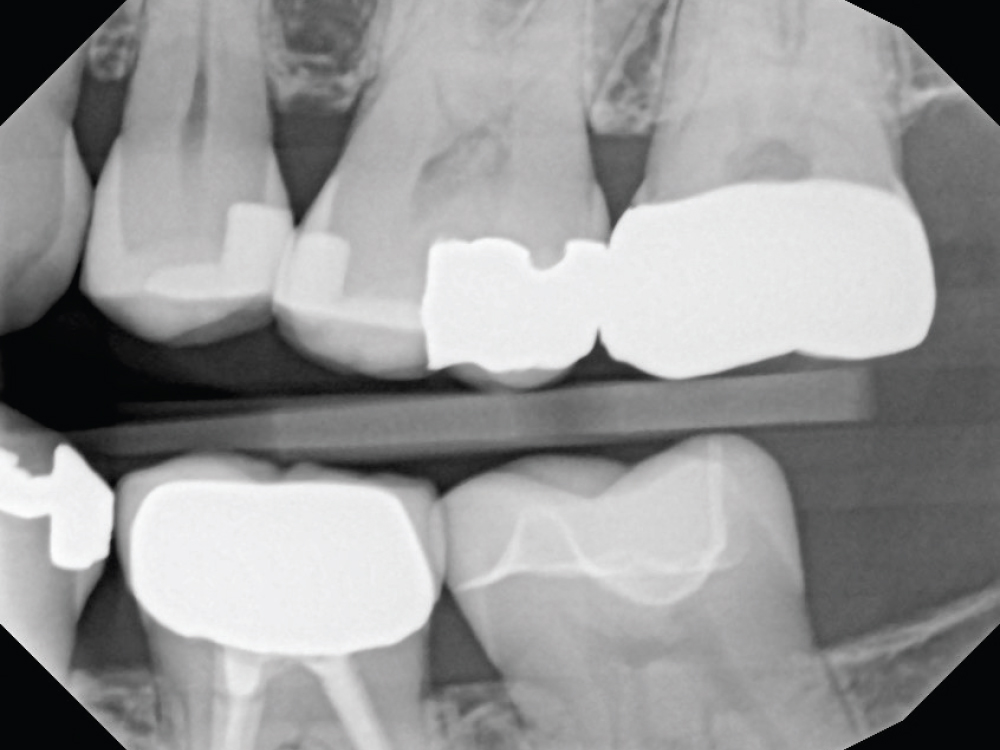

Even though she is a dental hygienist, Nikole decided to wait it out when she was told her crown on tooth #15 had an open margin. But over time, she noticed the area started to shred her floss. That’s when she decided it was time for the crown to be replaced.

Because the patient had high expectations for her restoration, I selected a BruxZir® Esthetic NOW Posterior Milling Block for its combination of esthetics and strength. Though BruxZir Esthetic was originally developed with the anterior in mind, with a yttria content that enhances the overall translucency and color, the material still maintains an excellent flexural strength of 870 MPa, meaning it is sufficiently strong enough to be used anywhere in the arch.